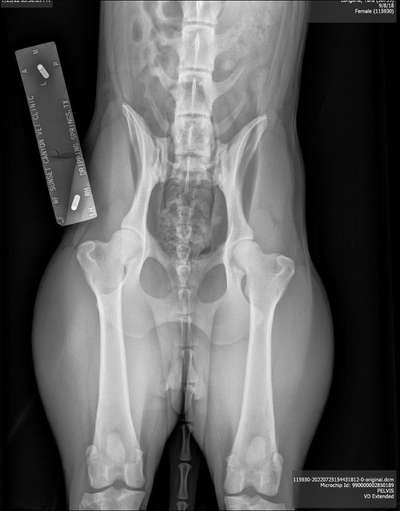

Ich habe leider nur das da könnt ihr mal fachsimpeln drüber 🙈